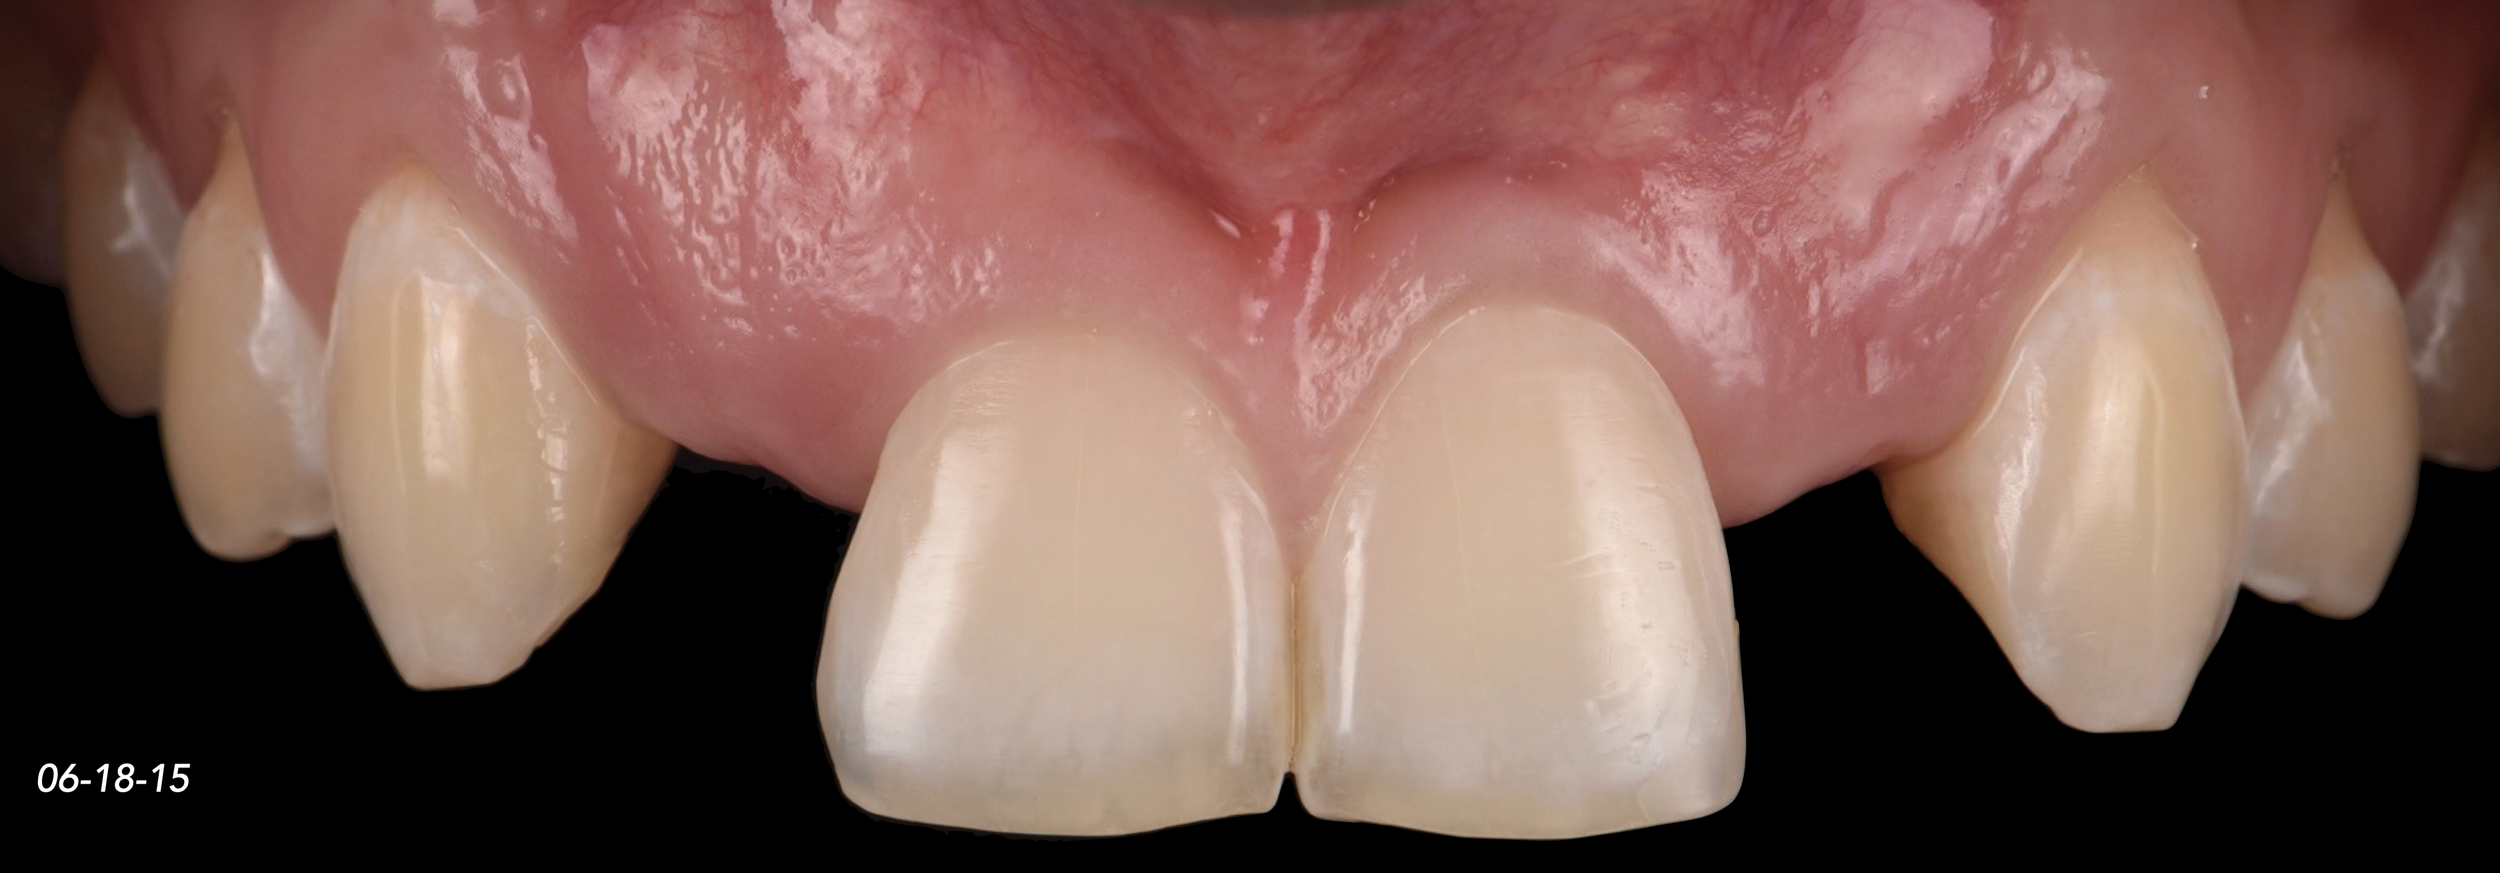

CASE 2. CONGENITALLY MISSING LATERAL INCISORS